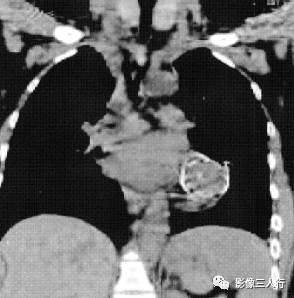

图6 畸胎瘤:胸部冠状面CT平扫可见中纵隔左心缘旁类圆形低密度影,边界清晰,其内密度不均匀,内部见骨样密度影,周边见壳状钙化